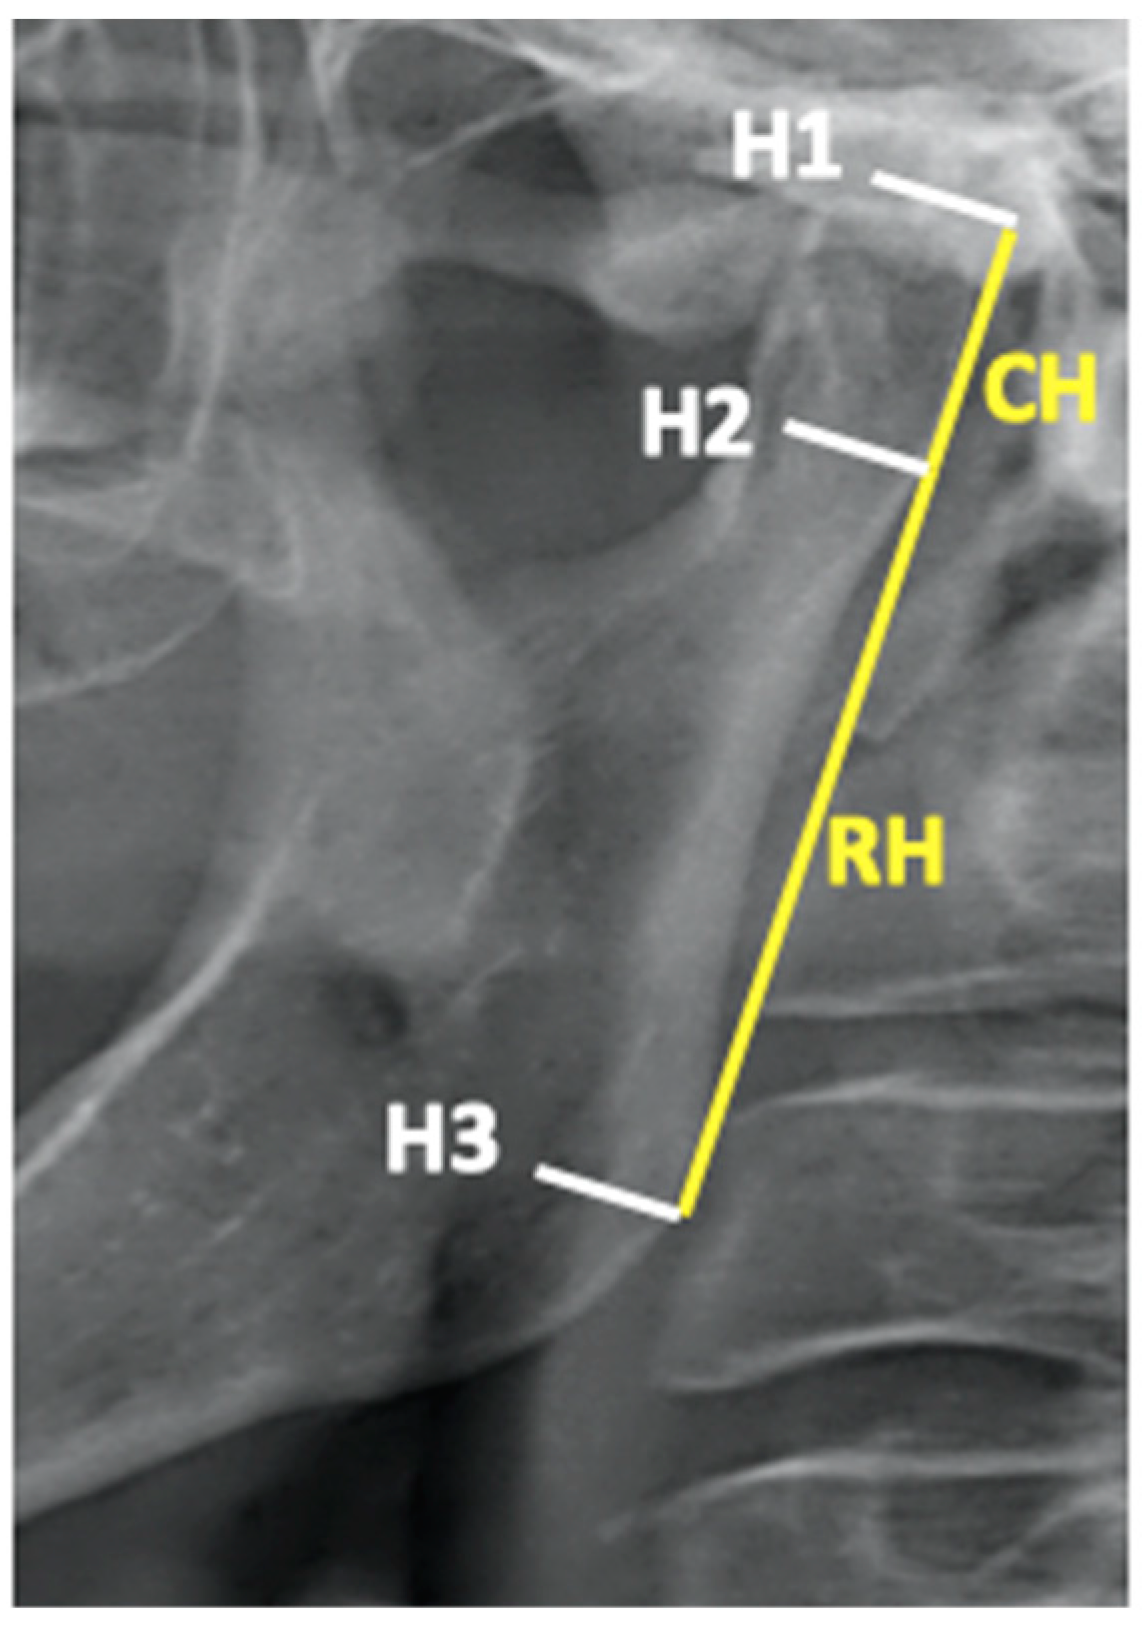

- Habets, L.L.M.H.; Bezuur, J.N.; VAN Ooij, C.P.; Hansson, T.L. The orthopantomogram, an aid in diagnosis of temporomandibular joint problems. I. The factor of vertical magnification. J. Oral Rehabil. 1987, 14, 475–480. [Google Scholar] [CrossRef] [PubMed]

- Habets, L.L.; Bezuur, J.N.; Naeiji, M.; Hansson, T.L. The Orthopantomogram, an aid in diagnosis of temporomandibular joint problems II. The vertical symmetry. J. Oral Rehabil. 1988, 15, 465–471. [Google Scholar] [CrossRef] [PubMed]